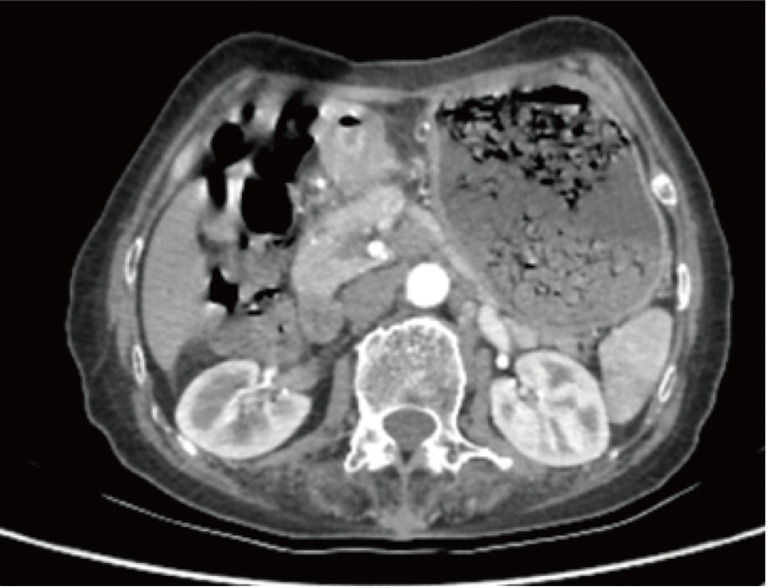

Figure 1.

Abdominal computed tomography showed gastric horn occupying lesion accompanied by multiple lymph node enlargement around the stomach before chemotherapy.